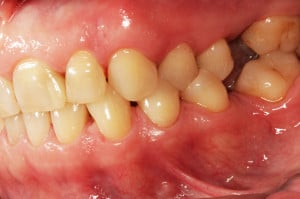

Do kliniki Stomatologia Bez Bólu zgłosiła się pacjentka, lat 61 z problemem nadwrażliwości zębów. Po przeprowadzonym wywiadzie stwierdzono spożywanie sporej ilości sezonowych owoców (truskawki, wiśnie, czereśnie, czarna porzeczka), nawet 3 razy dziennie. Następnie wykonano badanie wewnątrzustne. Stwierdzono obecność płytki nazębnej, ciemnego osadu oraz kamienia nazębnego na części trzonowców:

Wykonano higienizację jamy ustnej poprzez usunięcie kamienia nazębnego skalerem ultradżwiękowym, zdjęciem osadu i płytki nazębnej poprzez piaskowanie air flow plus oraz classic, a następnie wypolerowaniu gumką ze specjalistyczną pastą polerską: